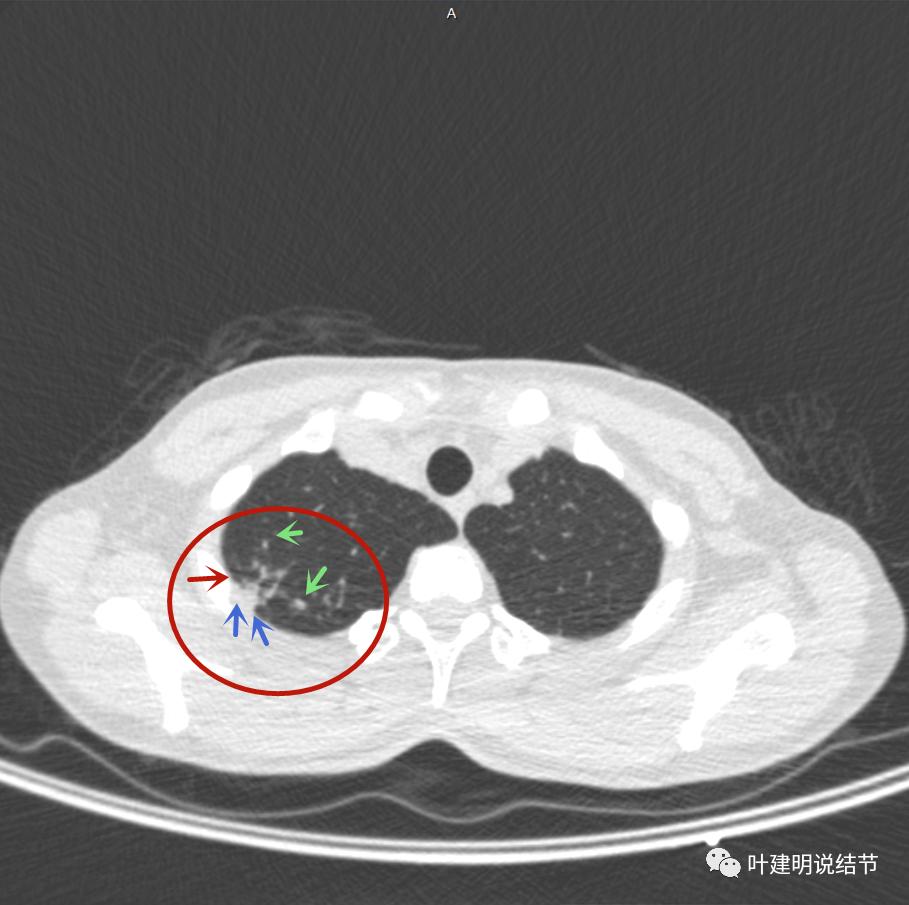

主病灶出现,粉色箭头示病灶密度较高,边上有磨玻璃影,甚淡(砖色箭头)

病灶有空洞(黄色箭头),主病灶边上见条索状高密度影(细红色箭头),邻近胸膜有粘连(蓝色箭头)

邻近胸膜明显增厚,且广基底,主病灶前方有小片磨玻璃影

主病灶与胸膜间基本相连,模糊清(蓝色箭头),主病灶壁厚薄欠均,边上有高密度条索状(桔色箭头)